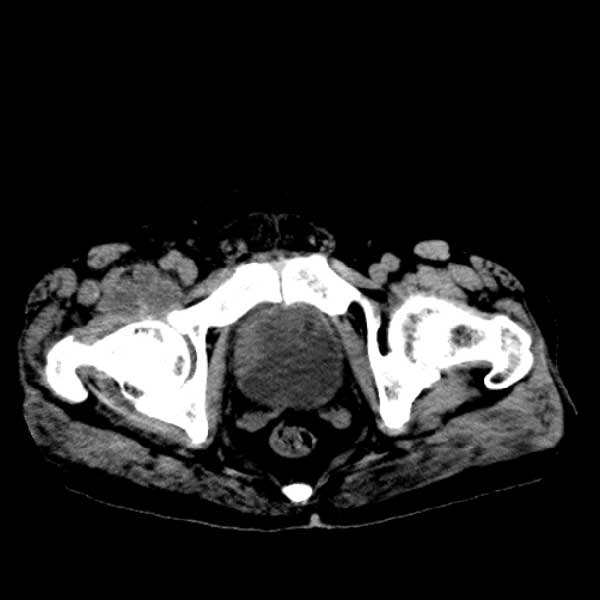

标题: CT13513:男 71 腹部疼痛20余天,近几天高热就诊,骨窗未见异 [打印本页]

标题: CT13513:男 71 腹部疼痛20余天,近几天高热就诊,骨窗未见异

考虑感染性病变可能性大,起源于阑尾?

感染,脓肿形成

考虑为化脓性阑尾炎.脓肿形成.及多肌肉累及.

考虑右侧腰大肌脓肿,向右髂窝、右腹股沟流注。

支持化脓性阑尾炎伴右髂窝脓肿、腰大肌腰方肌脓肿形成。

考虑腹腔及盆腔化脓性炎症,累及右侧髋关节及腹股沟区.

首先考虑化脓性阑尾炎伴腰大肌、腰方肌脓肿,不除外回盲部结核。

回盲部癌待排除。

患者肠镜检查考虑结肠癌,病理证实

患者肠镜检查考虑结肠癌,病理证实。肺部ct可见多发结节,考虑转移